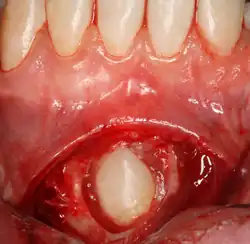

Sometimes, a surgeon may wish to expose the canine for aesthetic purposes. This may be achieved through open or closed exposure. Studies show no advantage of one method over another.[11] A laser can be used to uncover superficially impacted teeth with no bleeding and quick recovery.[12][13][14]